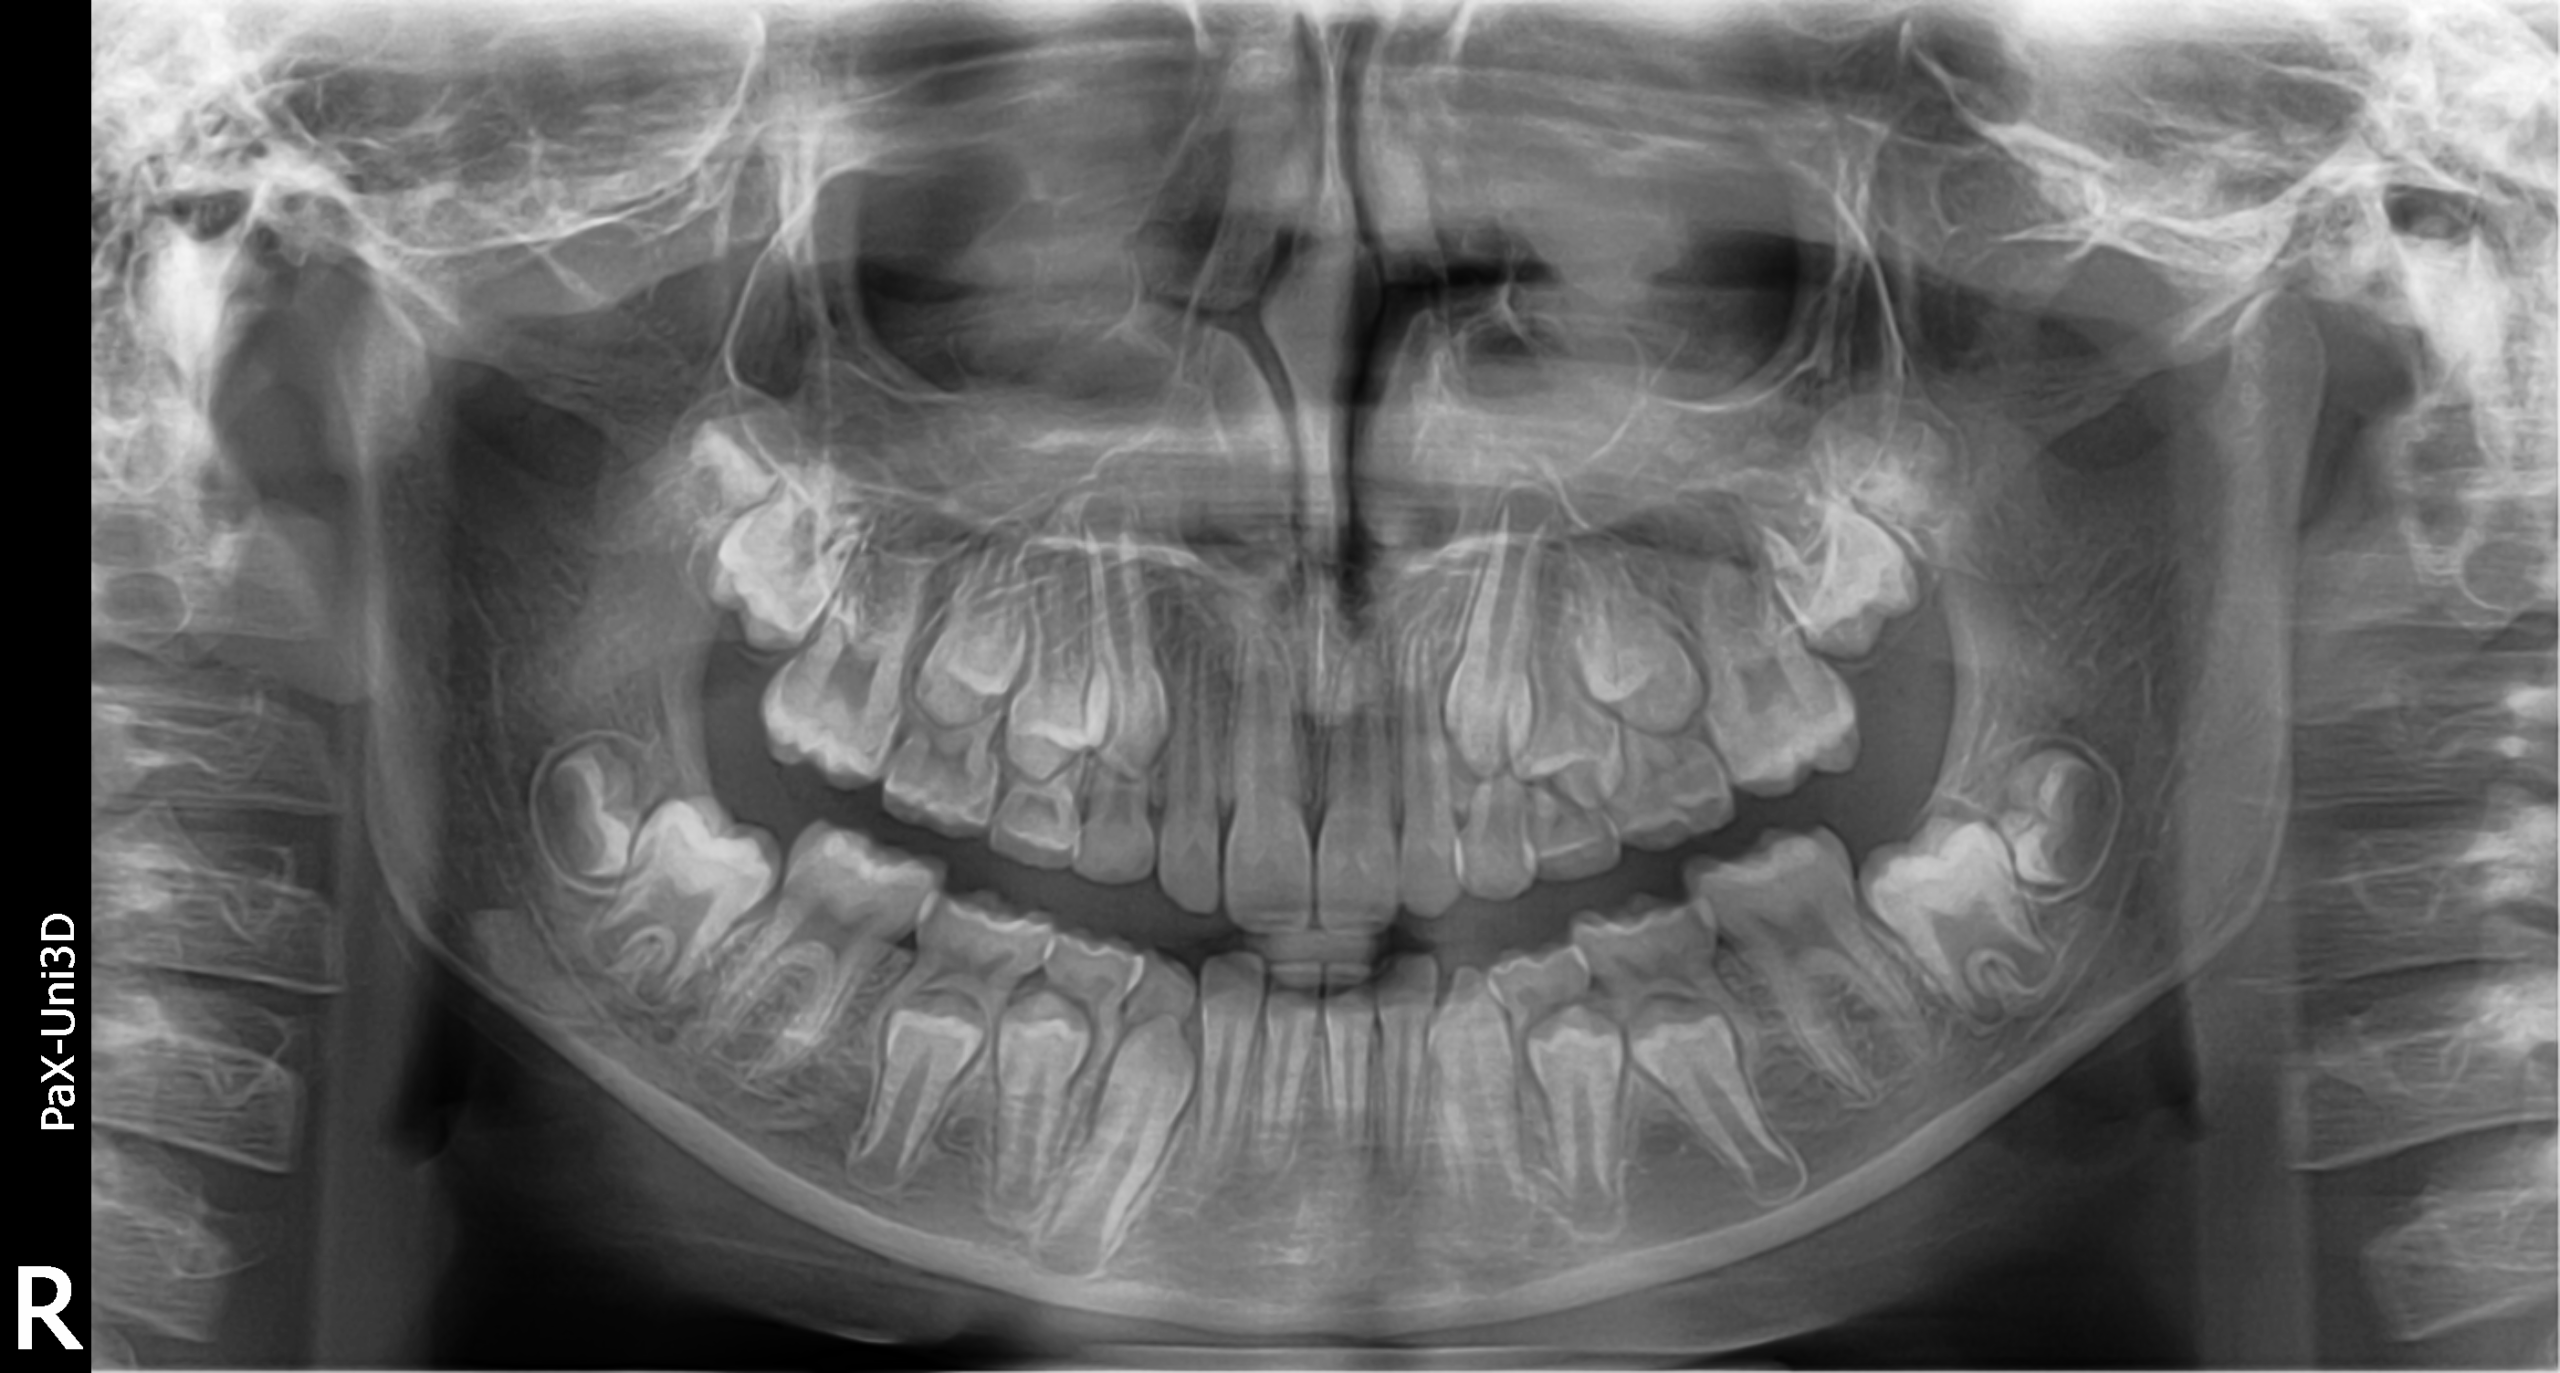

I_00000127 Ottobre 2025 by Studio Dentistico ZemellaArticoli correlati:ORTOGNATODONZIA risolta con la tecnica di ortopedia…